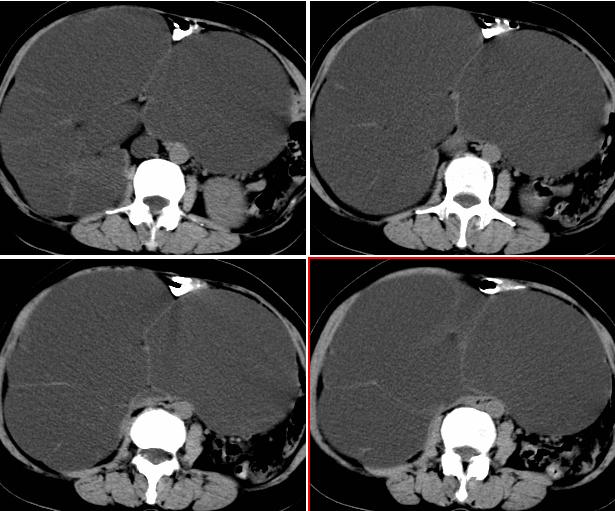

女,52岁,外伤后一小时入院,腹部b超示盆腹腔巨大无回声包块,右肾大小约208*107mm,追问病史,腹部逐渐隆8年余,无明显体重下降、消瘦、黑便呕血史,无大便性状改变,2年前已停月经,有高血压病史8年余,pe:血压180/100mmhg,全身皮肤粘膜无黄染、苍白,全身浅表淋巴结无肿大,腹部膨隆,呈蛙腹,可触及腹部有一14*15cm大小包块,质软,边界清楚,移动度可,无压痛,叩诊呈浊音。辅助检查:肝功能白蛋白43g/l球蛋白35.2g/l余指标正常,血糖电解质凝血四项正常。血常规hb115g/l白细胞13*10/9/l n0.85肾功能bun6.53mmol/l cr124umol/l.

右侧后腹膜巨大囊性肿块影阴,边缘清晰,内见膜状分隔,均匀水样密度,右肾影阴消失,囊块所到区域脏器受挤移位,右侧输尿管扩张,应该考虑:右肾重读积水,巨大肾囊肿不除外。引发肾性高血压。

腹部巨大囊性占位,膨胀性生长,边界光整,囊内容物为水样密度,其内可见多发分隔,纵观所有层面,正常右肾未见,考虑为来源于右肾的巨大多房性肾囊肿(多房性囊性肾瘤)可能性大。

该病来源和病因不明,儿童为先天性,多在5岁以下发病,成人多见于40-70岁女性,ct表现:单房或多房囊性病灶,有厚的囊壁,大部分有分隔,部分可出现环形、沙粒状钙化。

腹部巨大囊性占位,膨胀性生长,边界光整,囊内容物为水样密度,其内可见多发分隔,右恻输尿管全程扩张,纵观所有层面,正常右肾未见,考虑为来源于右肾的巨大多房性肾囊肿可能性大。

反推一下:1.那么重的积水,引起积水的原因大部分是右侧输尿管有梗阻,排出受阻。右侧输尿管应该也是重度扩张才对。2.如果是肾积水,而且是右侧输尿管问题引起,那么病人肯定有相应的临床症状:比如输尿管结石引起的血尿、剧痛等症状,至少也会急性发作病史。另,本例显然不需要考虑输尿管癌,膀胱也挺好,更没有无痛性血尿病史。病人8年多没有其他的不舒服,只是腹部日渐膨隆,临床症状显然不支持。3.如果是重度肾积水的话,应该可以看到被压缩的肾皮质,即使很菲薄也多少会有显示的。

右肾明显扩大,皮质菲薄,间隔细,右输尿管全程扩张,右肾重度积水,原因应重点查输尿管膀胱接合处。